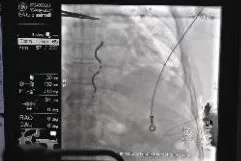

患者为61岁男性,一年前诊断冠心病并植入三枚支架,入院检查心脏超声EF 31%,动态心电图显示:室性早搏二联律,短阵室性心动过速。诊断为缺血性心肌病,为心脏性猝死的高危患者,术前影像学评估患者解剖适合EV-ICD的植入。 术前,新医大一附院汤宝鹏教授和手术团队与患者及家属进行充分沟通,同时多次与海内外专家、麻醉、医护团队进行了充分细致的案例讨论和手术操作复盘;术中,内外科团队紧密协作,EV-ICD植入手术过程顺利,胸骨下电极稳定,电学参数正常,除颤测试通过。患者于次日转回普通病房,优化各项参数,恢复良好。

汤宝鹏教授与李耀东教授为患者进行手术治疗

EV-ICD术中测试与术后影像